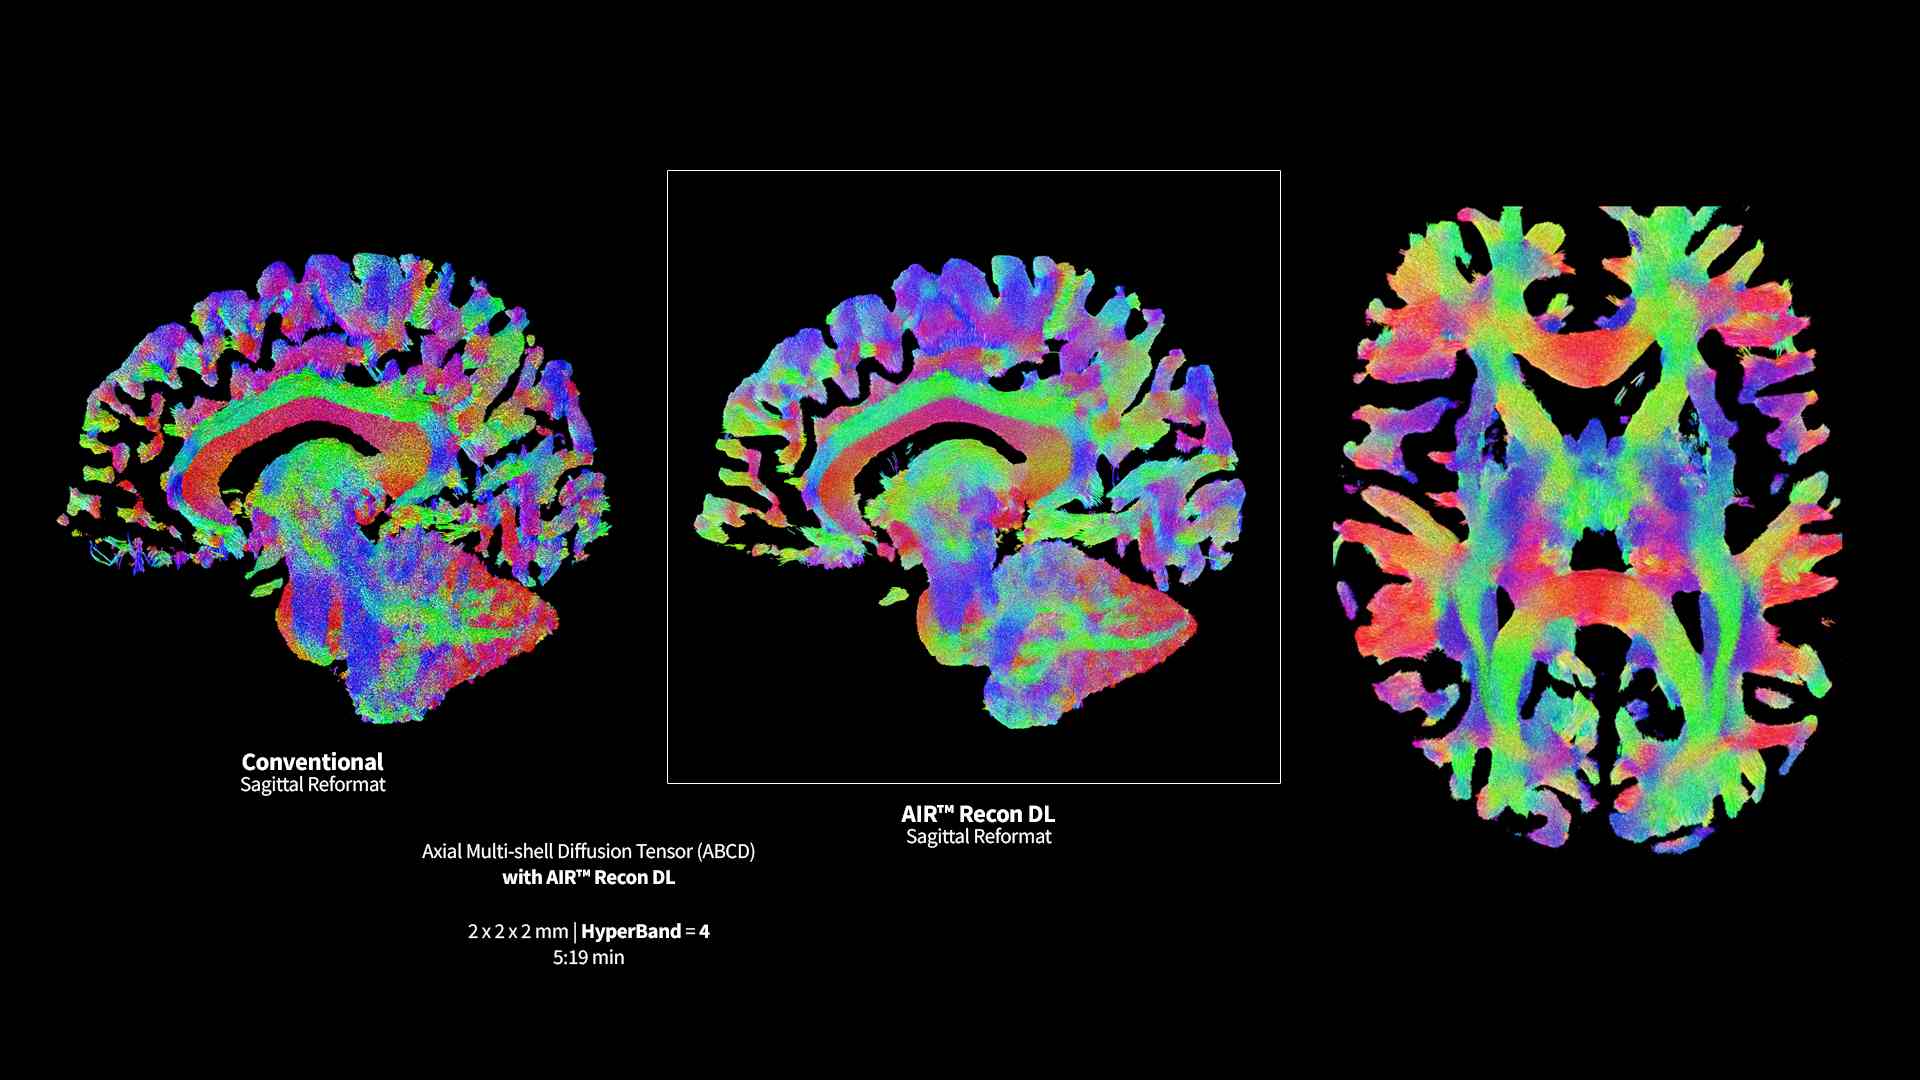

Clinical confidence

Revolutionary, deep-learning-based reconstruction techniques such as AIR™ Recon DL provide sharper, clearer, and accurate images